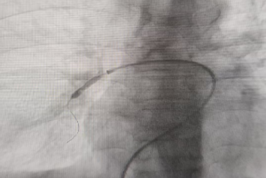

手术团队按 Seldinger 技术穿刺右侧股静脉,置入血管鞘,在右肺动脉处造影检查,发现右肺动脉多支血管狭窄,右下肺动脉狭窄严重,部分右下肺静脉也有轻微狭窄。术中采用分次逐级球囊扩张策略,将球囊精准放置于狭窄部位,术后造影显示,狭窄血管的 “蜂腰征” 消失,造影剂通过顺畅,手术成功。